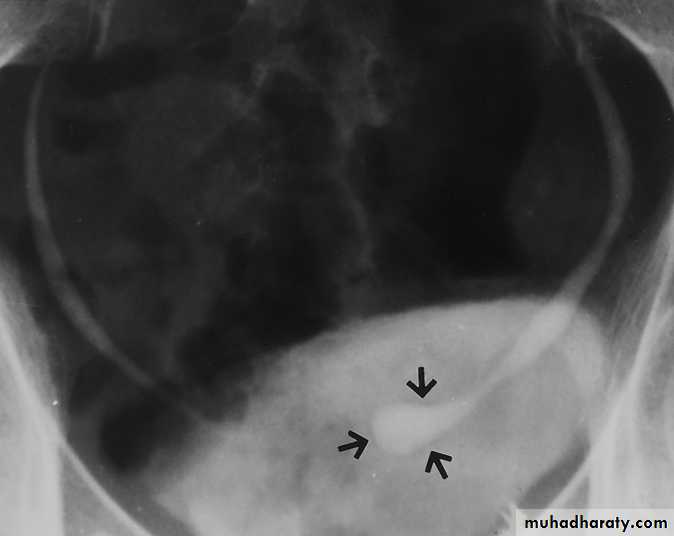

Ureterocele :

Congenital cystic dilatation of lower end of ureter ( intra-mural part) due to pin-hole meatus . May be simple or ectopic .

IVU :

- There is rounded or elliptical dilatation of lower end of ureter with thin lineal filling defect around it , resembling (cobra head appearance),

- Proximal dilatation of rest of ureter .

- In advanced cases hydronephrosis .

- In obstructed ureterocele , filling defect in the bladder